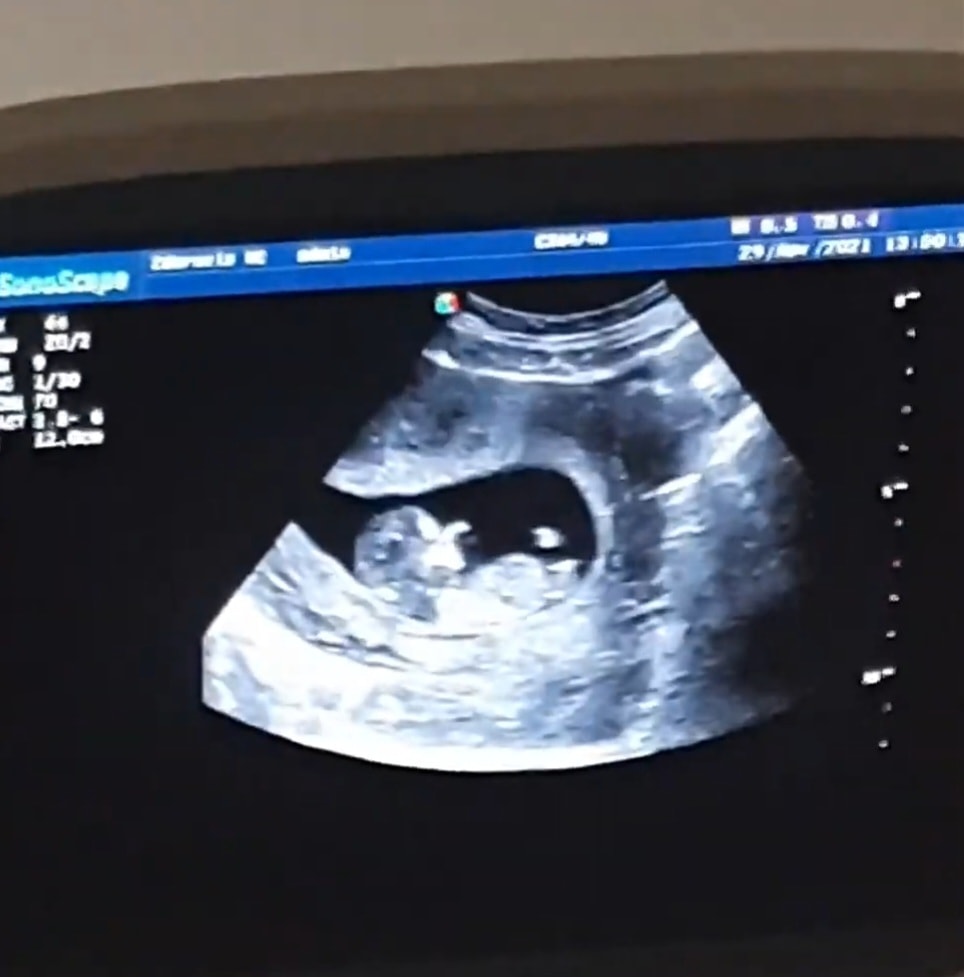

Пол узи 12 недель

Пол малышаСкрининг пройден, малыш в порядке, все риски низкие.🥰❤️ Я плакала ... 🥹 Спросила про пол, врач специально посметрела, по бугорку в 70% предположила девочку. 🥰 Девочки, у кого то было что бугорок палаллельно спинке, а в итоге мальчик. Или наоборот? В любом случае рады просто здоровому малышу, но хочется послушать. Фото приложила. 👇

Я думаю, что врач не ошибается. У пацана бугорок больше вверх торчит, чем параллельно позвоночнику.

Я бы сказала, что это 99% девочка)